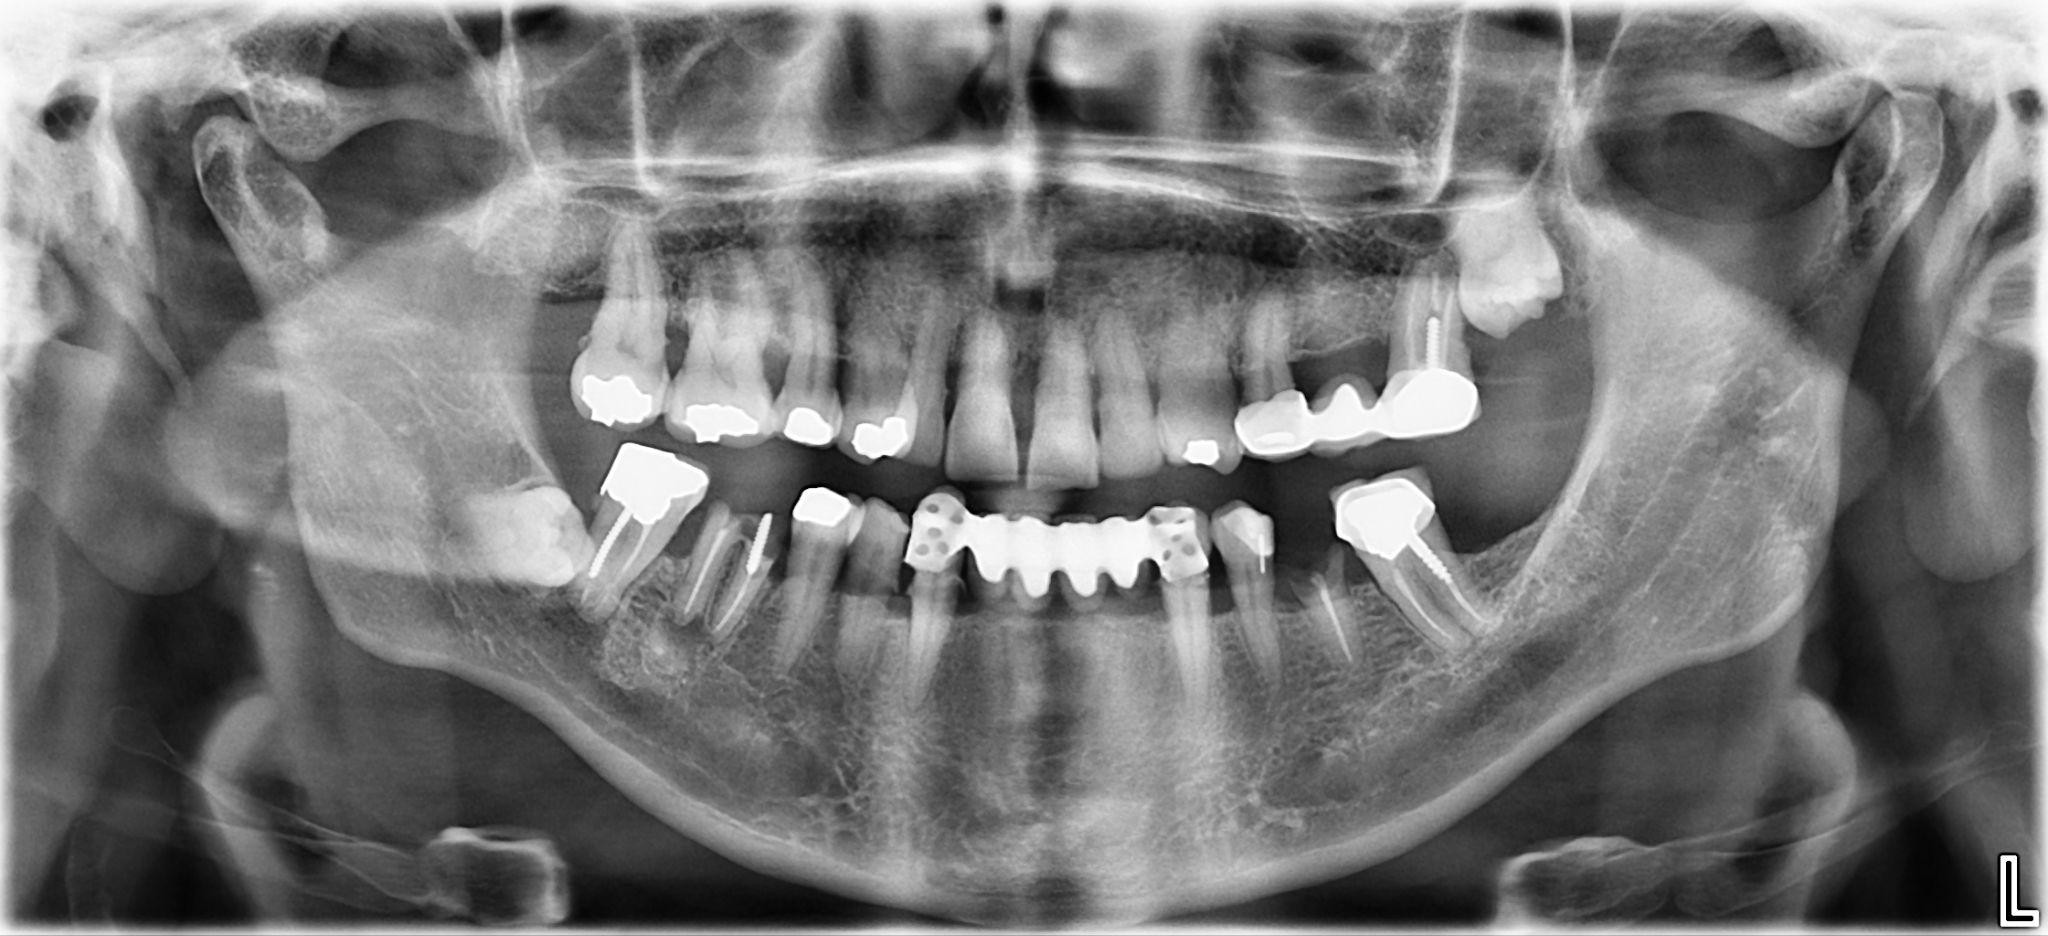

5. What option cannot be selected for the first quadrant of this panoramic X ray?

6. What option cannot be selected for the third quadrant of this panoramic X ray?

7. What option cannot be selected for the forth quadrant of this panoramic X ray?

8. What option cannot be selected for the upper jaw of this panoramic X ray?

9. What option cannot be selected for the lower jaw of this panoramic X ray?